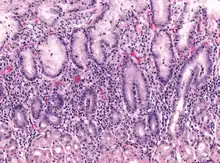

Metaplasia

Mucous gland metaplasia, the reversible replacement of differentiated cells, occurs in the setting of severe damage of the gastric glands, which then waste away (atrophic gastritis) and are progressively replaced by mucous glands. Gastric ulcers may develop; it is unclear if they are the causes or the consequences. Intestinal metaplasia typically begins in response to chronic mucosal injury in the antrum and may extend to the body. Gastric mucosa cells change to resemble intestinal mucosa and may even assume absorptive characteristics. Intestinal metaplasia is classified histologically as complete or incomplete. With complete metaplasia, gastric mucosa is completely transformed into small-bowel mucosa, both histologically and functionally, with the ability to absorb nutrients and secrete peptides. In incomplete metaplasia, the epithelium assumes a histologic appearance closer to that of the large intestine and frequently exhibits dysplasia.[20]